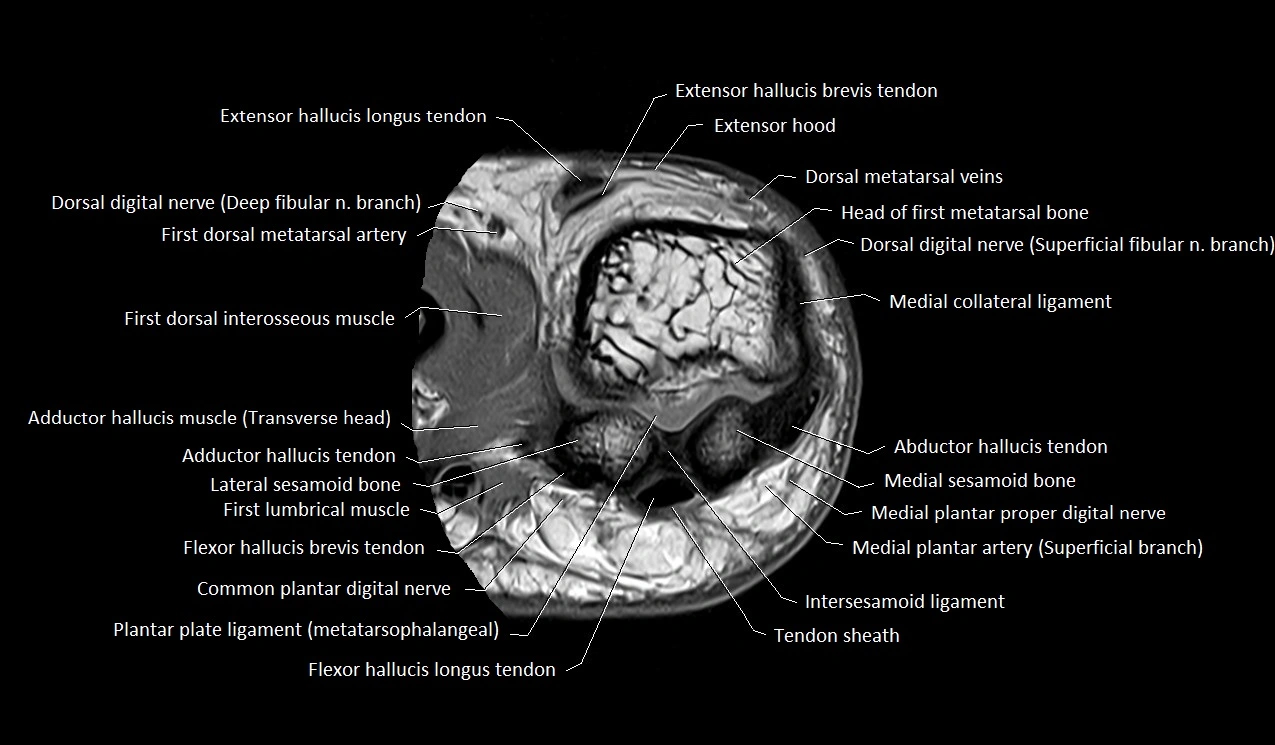

MRI image

image